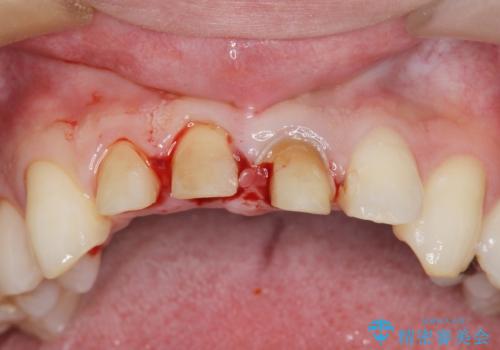

・歯肉縁下カリエス →部分矯正による歯の挺出・歯周外科

歯の挺出を行ったことで歯ぐきの腫れも改善され、安定した歯周環境下でのセラミッククラウン治療を行うことができました。

- 外科手術のため、術後に出血、痛みや腫れ、違和感を伴います